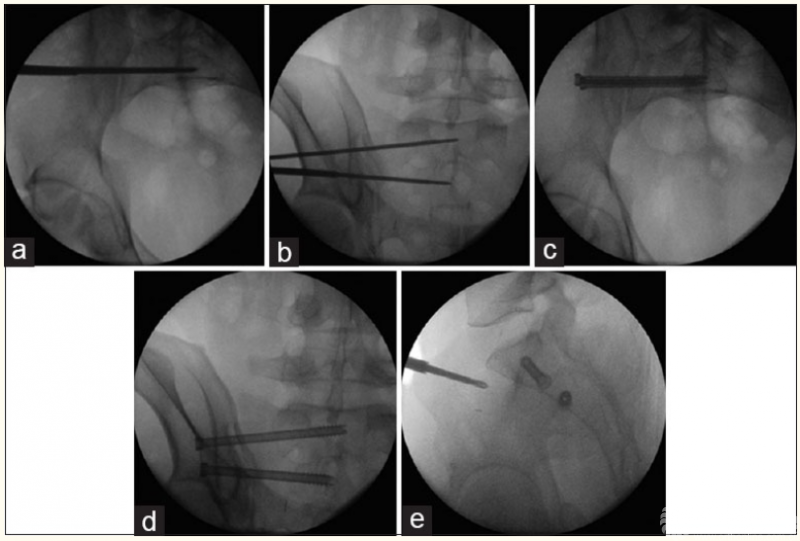

1、肘关节旋转轴三维定位

国内蒋协远教授团队在世界上率先采用三维导航机器人进行肘关节旋转中心定位。TiRobot机器人导航辅助肘关节旋转中心轴定位能够极大地降低主观判断造成的旋转轴偏移,提高轴心定位精准度,减少反复透视验证的过度辐射及反复调整轴心导针的骨质破坏,避免可能的血管、神经损伤,显著减小降低术后肘关节活动阻力,并减少外固定针松动、断裂及外固定架断裂等并发症的发生率,从而整体提高治疗效果。